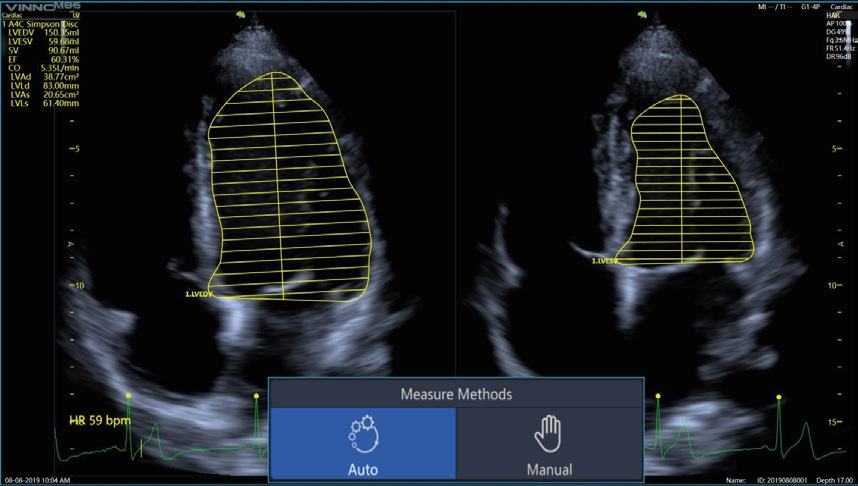

- STRAIN / AUTOEF / STRESS ECHO - son herramientas avanzadas para estudios ecocardiograficos especializados, disponibles en los portátiles V6 y V8, ademas de varios modelos de rodantes.

Para ecocardio, estos equipos disponen tambien de un transductor Phase Array "S1-6P",

con tecnología de cristal único (Single Crystal), fabricado en exclusivo para VINNO, por VERMON S.A. en Francia.

El transductor "S1-6P" tiene una frecuencia de 2 a 6 MHz., un angulo de apertura de 90º, logrando imágenes de excelente calidad.

Vinno cuenta con Sonda Transesofágica, TEE de origen U.S.A. para sus equipos configurados para cardiología.